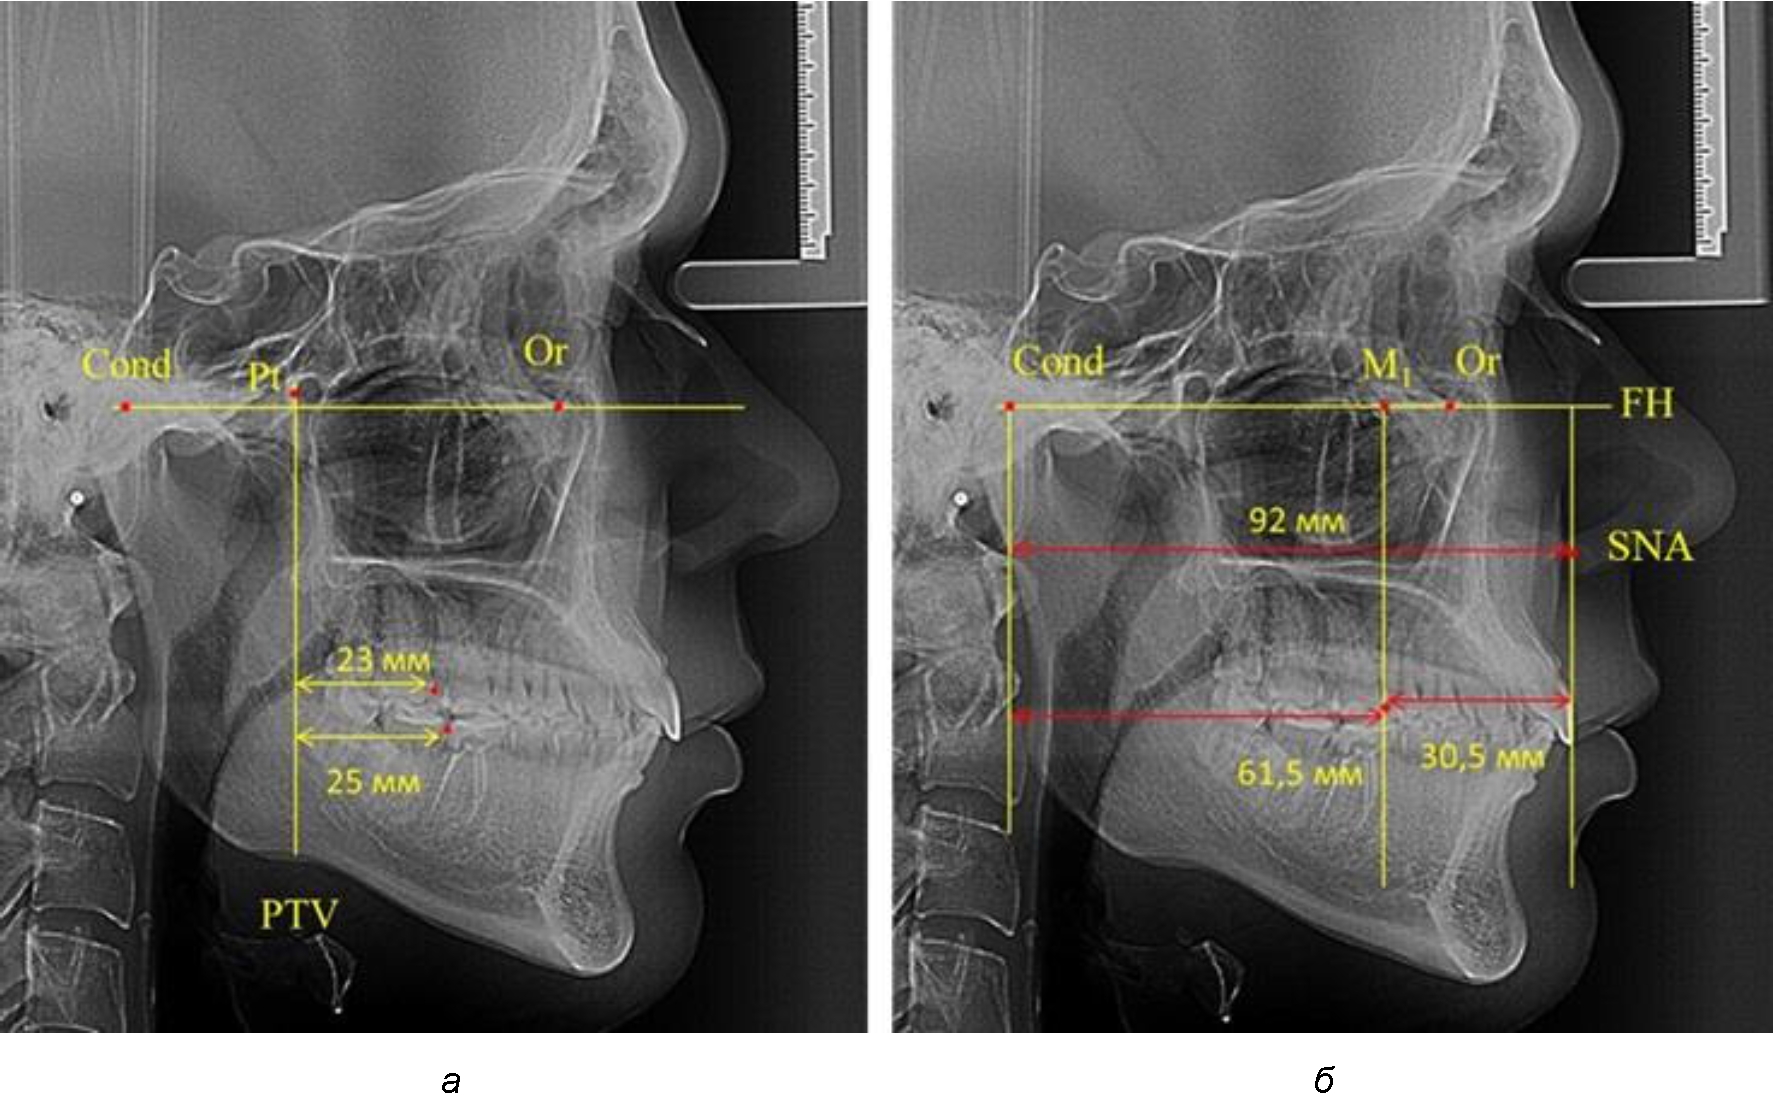

Согласно указанному методу на рентгенограммах проводили Франкфуртскую горизонталь. Учитывая мнения специалистов относительно ориентиров для построения и вариабельность положения наружного слухового прохода, в качестве задней точки использовали верхнюю выпуклость суставной головки нижней челюсти («Cond»). Передняя точка традиционно располагалась на нижнем крае глазницы и определялась как орбитальная точка Or.

Находили положение точки Pt, которая располагалась на пересечении нижнего края круглого отверстия и задней стенки крыловидно-верхнечелюстной щели, и перпендикулярно к Франкфуртской горизонтали проводили крыловидную вертикальную линию, которую принято обозначать как плоскость PTV. Расстояние от крыловидной вертикальной плоскости PTV до дистальной поверхности верхнего первого постоянного моляра определяло его положение, которое, по мнению R. E. McDonald, соответствовало возрасту пациента, увеличенному на 3 мм.

При проведении анализа к Франкфуртской горизонтали проводили передний и задний перпендикуляры. Передний спинальный перпендикуляр проходил через выступающую точку передней носовой ости (spina nasalis anterior – SNA), а задний суставной перпендикуляр опускали из кондилярной точки Cond. Молярный перпендикуляр проводили через медиальную поверхность первого постоянного моляра. Указанная вертикаль отделяла замещающие зубы постоянного прикуса от добавочных зубов (постоянных моляров), что вполне логично для анализа положения первых постоянных моляров в гнатическом комплексе (рис. 1).

Рис. 1. Метод определения положения первых верхних моляров по Ralph E. McDonald (а) и по предложенному методу (б)

Анализ проведенного исследования рентгенограмм показал существенную вариабельность практически всех линейных показателей. У молодых людей с физиологическим прикусом постоянных зубов расстояние от крыловидной вертикальной плоскости PTV до дистальной поверхности верхнего первого постоянного моляра в целом по группе составляло (18,37 ± 3,62) мм. Обращает на себя внимание большая ошибка репрезентативности из-за разницы между максимальными и минимальными значениями.

Среди анализируемых рентгенограмм минимальное значение расстояния по методу R. E. McDonald было 12 мм, а максимальное достигало 25 мм, что, по нашему мнению, обусловлено вариабельностью сагиттального размера гнатического отдела лица.

Таким образом, для прогнозирования оптимального положения первых постоянных моляров наиболее целесообразным методом явилось использование относительного показателя, что подтверждено при анализе рентгенограмм с минимальными и максимальными значениями по методу R. E. McDonald.

Так, при расстоянии от крыловидной вертикальной плоскости PTV до дистальной поверхности верхнего первого постоянного моляра в 13 мм сагиттальный размер гнатического отдела был 82 мм. При этом отношение кондилярно-спинального расстояния к кондилярно-молярному размеру (54,5) было близким к коэффициенту 1,5, что представлено на рис. 2.

В то же время при увеличенном расстоянии от крыловидной вертикальной плоскости PTV до дистальной поверхности верхнего первого постоянного моляра, равное 23 мм, сагиттальный размер гнатического отдела составил 92 мм. При этом отношение кондилярно-спинального расстояния к кондилярно-молярному размеру (30,5), так же, как и при малых размерах, было близким к коэффициенту 1,5, что представлено на рис. 3.